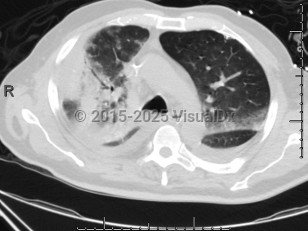

Chlamydophila pneumoniae pneumonia

Chlamydophilia pneumoniae (also known as Chlamydia pneumoniae) is an obligate intracellular bacterium that causes pneumonia.

Many patients infected with this pathogen are likely asymptomatic or minimally symptomatic. In symptomatic patients who present for evaluation, fever, cough, and dyspnea are seen. Cough is often nonproductive and may persist for weeks despite therapy.